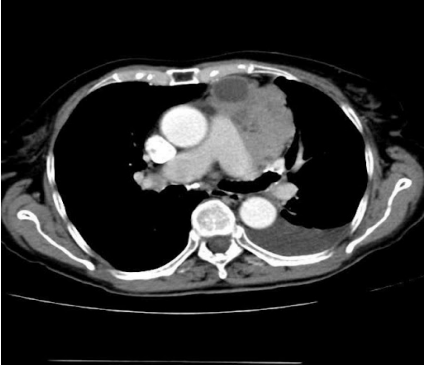

Linfoma ao lado direito do mediastino. Fonte: Acervo de aulas do Grupo MedCof.